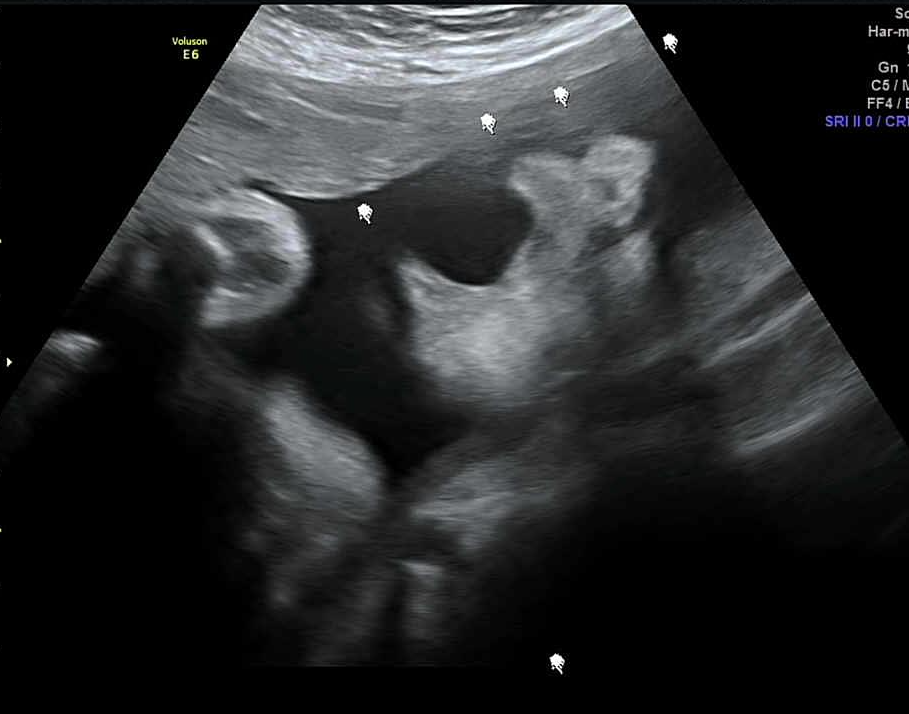

[임신 9개월 태아 초음파 막달검사 후기]

임신 32주 4일째 초음파 촬영을 했다. 이전과는 달리 확연하게 눈, 코, 입을 명확히 구분할 수 있었다. 초음파 촬영 중 하품하는 모습을 보여주었다. 태아의 몸무게는 2kg 였다.

임신 34주 6일째 정기검진을 통해 한 번 더 초음파 촬영을 했다. 2주만에 태아의 몸무게는 2.4kg으로 400g이 증가되어 있었다. 막달검사(분만전검사)는 출산에 관련 된 중요한 검사로, 34주~36주 사이에 진행한다. 검사에 이상이 있는 경우 미리 조치를 취하여 안전한 출산을 도모한다. 막달검사를 통해 x-ray촬영(심장,폐 검사. 배 가리고 진행), 소변검사, 혈액검사, 심전도검사를 진행했다.